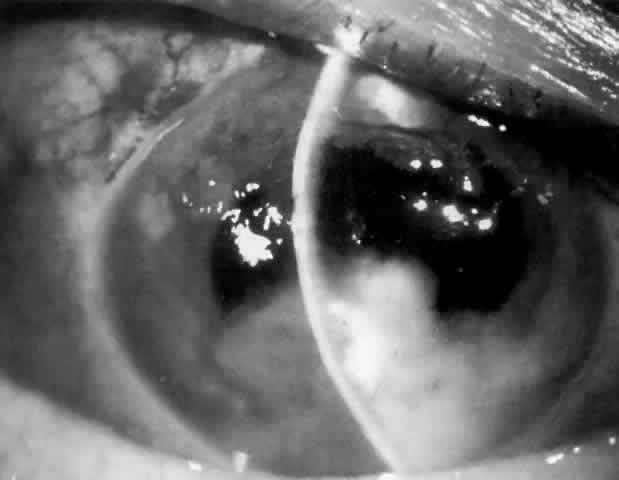

MANAGEMENT. Laser peripheral iridectomy quickly resolves pupillary block (Figs. 6 and 7). Because of inflammation and iridocorneal contact peripherally, this procedure may be difficult to accomplish. If the view is inadequate or a laser is not available, pupillary dilation with phenylephrine will in some cases relieve pupillary block (Figs. 8 and 9). Ultimately the patient will need a laser peripheral iridectomy. If peripheral anterior synechiae have formed or the IOP elevation persists after relief of the pupillary block, the patient will require management similar to that used in chronic angle-closure glaucoma.

Fig. 6. Pupillary block with iris bombé around haptics of anterior chamber lens implant, resulting in elevated intraocular pressure.

Fig. 7. Resolution of pupillary block after laser peripheral iridectomy.

Fig. 8. Iris bombé nasal to anterior chamber lens implant before dilation (shadowed area on right). No peripheral iridectomy is present.

Fig. 9. Resolution of pupillary block and iris bombé after pupillary dilation. A subsequent laser peripheral iridectomy was performed.